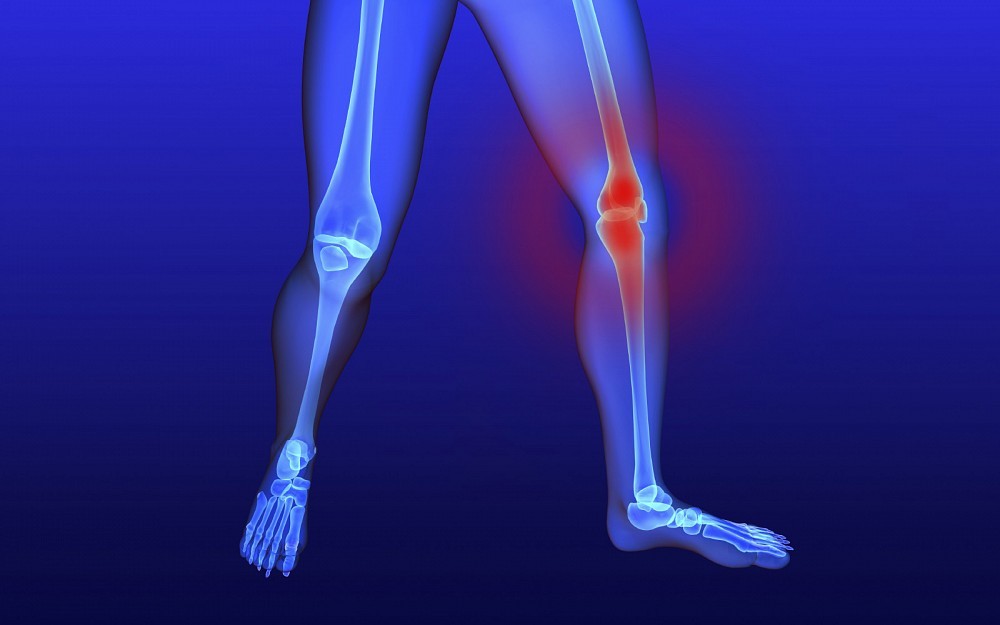

CINCINNATIComplaints about knee pain can be all too familiar when you suffer from osteoarthritis of the knee. The condition often keeps sufferers from participating in many activitiessometimes even just standing.

OA is a chronic condition characterized by the breakdown of the joints cartilage. The breakdown of cartilage causes the bones to rub against each other, leading to stiffness, pain and loss of movement in the joint.

Typically, she says, the pain associated with osteoarthritis of the knee is managed by the use of non-steroidal anti-inflammatory medications with brand names such as Motrin, Advil or Aleve, which target inflammation around the site. New treatment approaches strongly suggest the pain can be medicinally managed from the central nervous system, such as with fibromyalgia, she says.